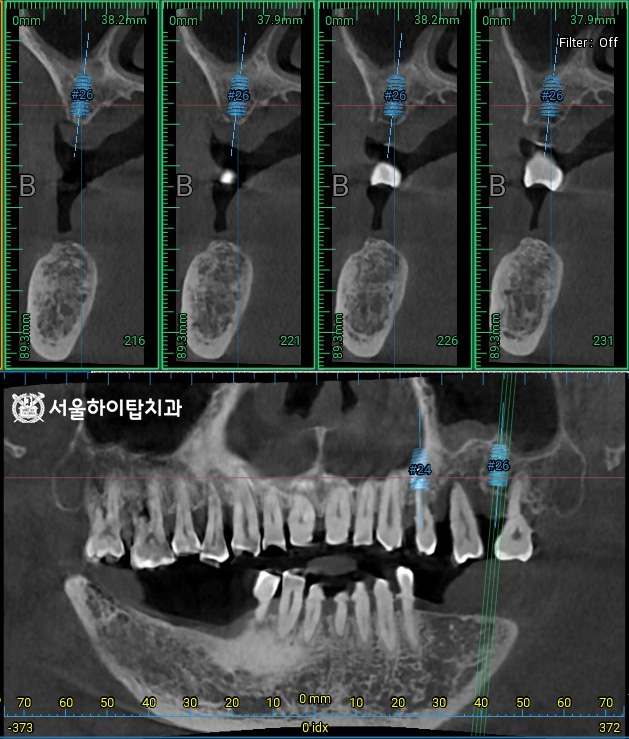

이와 함께, CT 촬영을 통해

픽스처가 식립될 위치를

사전에 시뮬레이션할 수 있습니다.

주안동 치과 에서는 이를 통해

잔존 치조골의 높이, 밀도, 두께,

해부학 구조물 등을 면밀히 분석하고,

시술 과정과 보철 설계를 정확하게

계획할 수 있다고 설명드립니다.